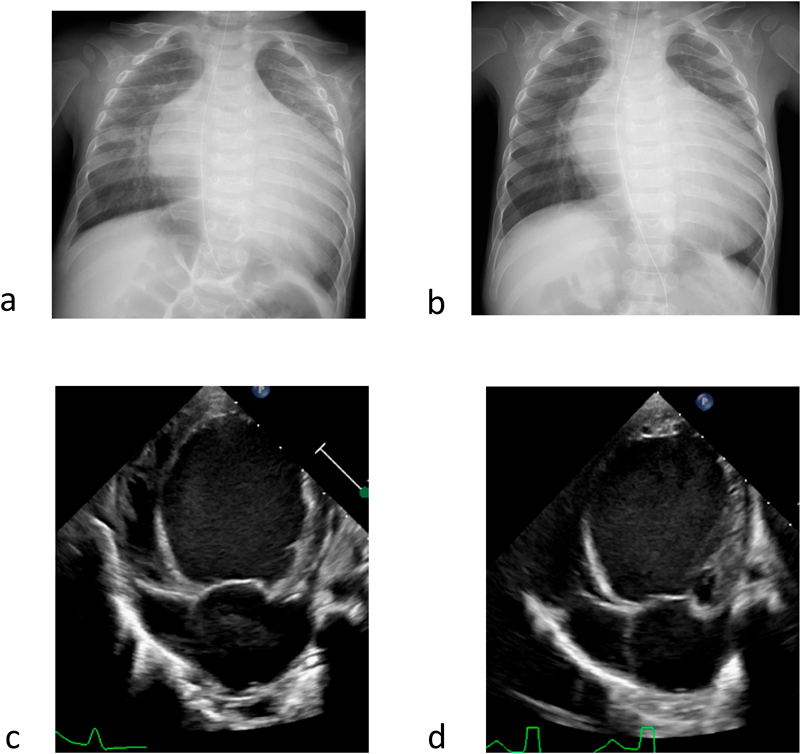

特発性拡張型心筋症に対し肺動脈絞扼術を施行した1乳児例Pulmonary Artery Banding in an Infant with Idiopathic Dilated Cardiomyopathy